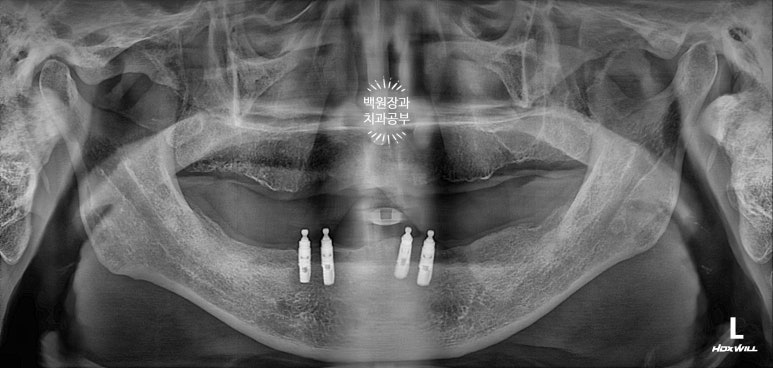

위턱은 전체 틀니를 사용하고 계셨고, 아래턱에는 임플란트 틀니 (오버덴처)를 사용하고 계셨습니다.

아래턱은 임플란트 네개가 있었지만, 위치가 약간 제각각이네요.

정면과 측면 구강 내 사진입니다. 아래 임플란트가 임플란트 주위염을 앓고 있어 보이지 말아야 할 임플란트의 뿌리부분이 보이네요...